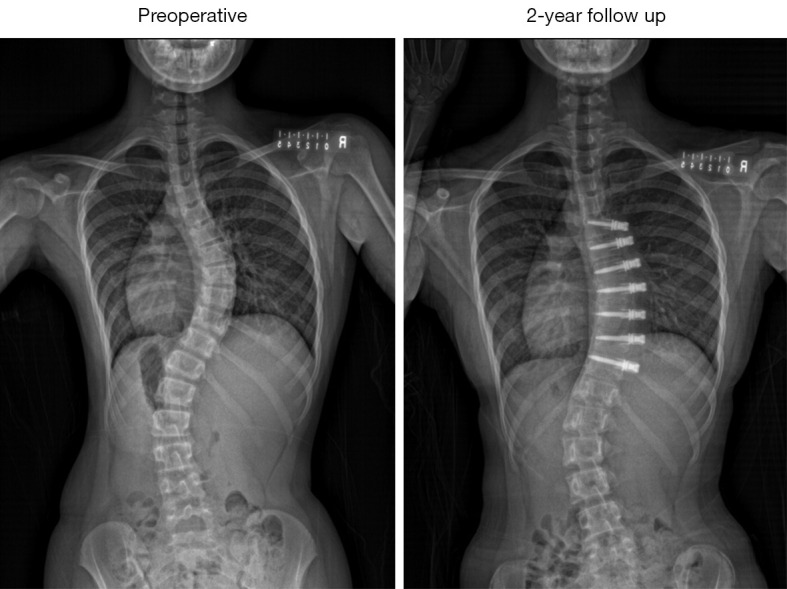

Background: Vertebral body tethering (VBT) has shown improvements in coronal and sagittal plane correction in adolescent idiopathic scoliosis (AIS) patients, but axial correction over time remains unexplored. Three-dimensional (3D) spine reconstruction was used to analyse correctional changes in all spinal planes post VBT surgery.

Case description: AIS subjects who underwent thoracic VBT surgery with a minimum 2-year follow-up were assessed. Biplanar radiographs were used for 3D spinal reconstructions, 3D coronal, sagittal thoracic kyphosis (TK), lumbar lordosis (LL), and axial rotation measurements were compared at pre-operative (pre-op), immediate post-operative (post-op), 1-year, and 2-year follow-up. Eight patients (7 females, 1 male) with a mean age of 11.8±1.3 years with right thoracic curves (mean 50.4°±8.1°) were followed for 26.8±4.1 months. Mean coronal Cobb angle showed significant improvement: 28.4°, 19.2°, and 27.1° at post-op, 1-year, and 2-year follow-up (P<0.001). Minimal changes were seen in sagittal plane: TK-35.2°, 39.0°, 31.3°, 37.0°; LL-46.1°, 42.8°, 36.5°, 42.8° (pre-op, post-op, 1-year, 2-year) respectively. Apical axial rotation improved from -5.5°±5.0° to -1.4°±4.8° post-op, then deteriorated to -3.2°±4.9° at 1 year and -7.0°±5.9° at 2 years, with no significant changes.

Conclusions: This is the first case series to use 3D radiographic digital measurements to reveal apical axial rotation progression in thoracic curves despite improved coronal curvature. While larger scales studies with longer follow-up are needed to verify our findings, surgeons and patients should be aware of such findings in their decision to select VBT as their procedure of choice.